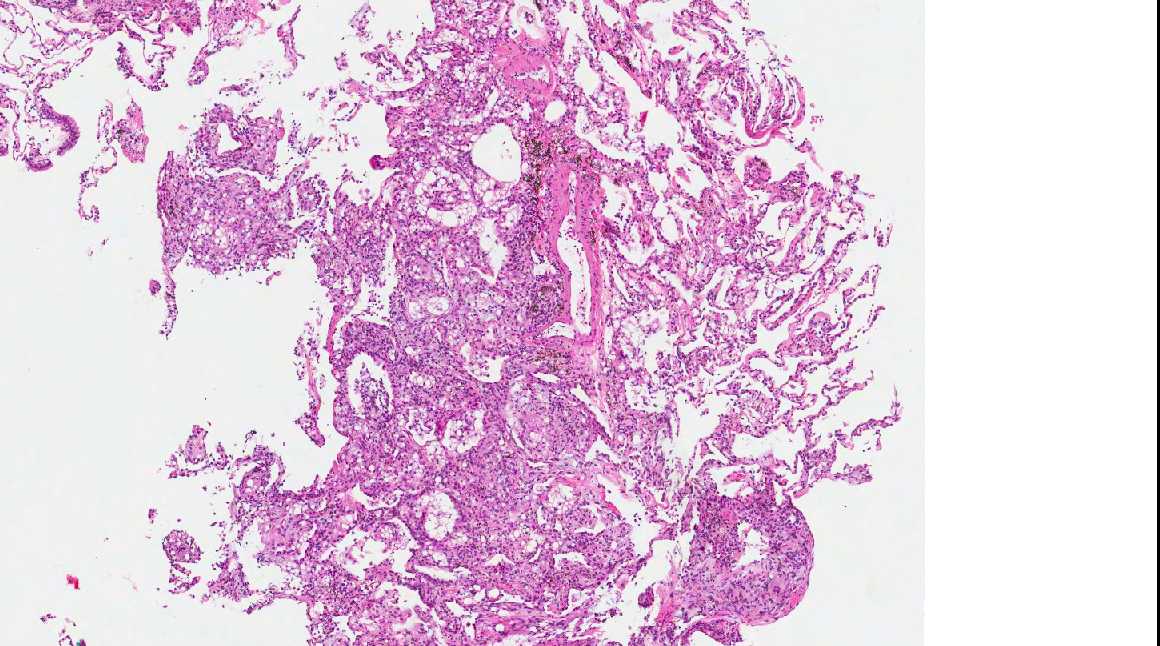

A 71 year old man with recent history of meningitis presented with recurrent episodes of pneumonia. High resolution CT scans showed crazy paving and tree in bud images. The patient underwent a transbronchial biopsy.

Micro images:

Diagnosis: Aspiration with granulomatous bronchiolitis and lipoid pneumonia

Aspiration of particulate matter, traditionally observed at autopsy, has also been described in debilitated patients, who often have a history of recurrent pneumonia, which is often unrecognized (Am J Surg Pathol 2007;31:752, Am J Surg Pathol 2010;34:1456). It usually (88%) shows bronchiolitis obliterans organizing pneumonia, often with multinucleated giant cells, acute bronchopneumonia / bronchiolitis or suppurative granulomas. Foreign material is usually but not always present (Am J Surg Pathol 2011;35:426).

The differential diagnosis of pulmonary granulomatous inflammation is broad and requires special stains, culture and clinical correlation (Ann Diagn Pathol 2003;7:127, Histopathology 2007;50:289).

Lipoid pneumonia is often an incidental postmortem finding associated with debilitating disease. The lipid may be exogenous (from nasal sprays or inhalation of other lipid containing substances) or endogenous (bronchial obstruction).

A 71 year old man with recent history of meningitis presented with recurrent episodes of pneumonia. High resolution CT scans showed crazy paving and tree in bud images. The patient underwent a transbronchial biopsy.

Micro images:

Diagnosis: Aspiration with granulomatous bronchiolitis and lipoid pneumonia

Aspiration of particulate matter, traditionally observed at autopsy, has also been described in debilitated patients, who often have a history of recurrent pneumonia, which is often unrecognized (Am J Surg Pathol 2007;31:752, Am J Surg Pathol 2010;34:1456). It usually (88%) shows bronchiolitis obliterans organizing pneumonia, often with multinucleated giant cells, acute bronchopneumonia / bronchiolitis or suppurative granulomas. Foreign material is usually but not always present (Am J Surg Pathol 2011;35:426).

The differential diagnosis of pulmonary granulomatous inflammation is broad and requires special stains, culture and clinical correlation (Ann Diagn Pathol 2003;7:127, Histopathology 2007;50:289).

Lipoid pneumonia is often an incidental postmortem finding associated with debilitating disease. The lipid may be exogenous (from nasal sprays or inhalation of other lipid containing substances) or endogenous (bronchial obstruction).